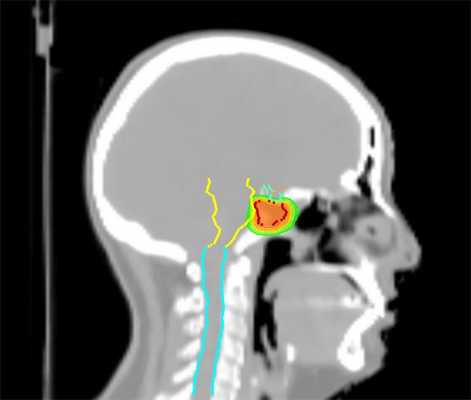

Tomotherapy в лечении доброкачественных опухолей головного мозга

Tomotherapy — это принципиально новая концепция лучевой терапии, которая сочетает элементы КТ-сканера с линейным ускорителем, чтобы точно скорректировать положение мишени и органов, находящихся в зоне риска, непосредственно перед лечением. Это особенно важно в отношении опухолей основания черепа, где они располагаются вблизи жизненно важных структур ствола мозга.

Tomotherapy уже активно применяется в ведущих онкоцентрах мира, где позволяет добиться хорошего результата лечения. Так, Джейкоб Ван Дейк из университета Онтарио сообщает об успешном облучении низко злокачественной глиомы и астроцитом, отмечая сохранение здоровой ткани. Аналогичные результаты получены и специалистами из других стран, что открывает принципиально новые возможности применив лучевой терапии.